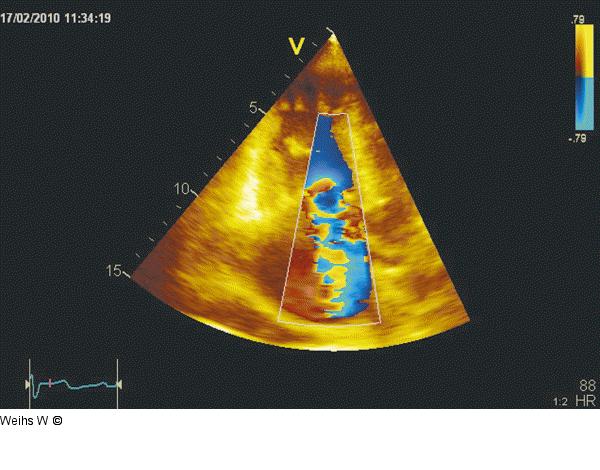

Abbildung 5: Trikuspidalinsuffizienz Darstellung der schweren Trikuspidalinsuffizienz im apikalen Schnitt. Die Trikuspidalinsuffizienz füllt den Großteil des rechten Vorhofes aus (>10 cm2), die Vena contracta misst > 1,0 cm. |

Darstellung der schweren Trikuspidalinsuffizienz im apikalen Schnitt. Die Trikuspidalinsuffizienz füllt den Großteil des rechten Vorhofes aus (>10 cm2), die Vena contracta misst > 1,0 cm. |